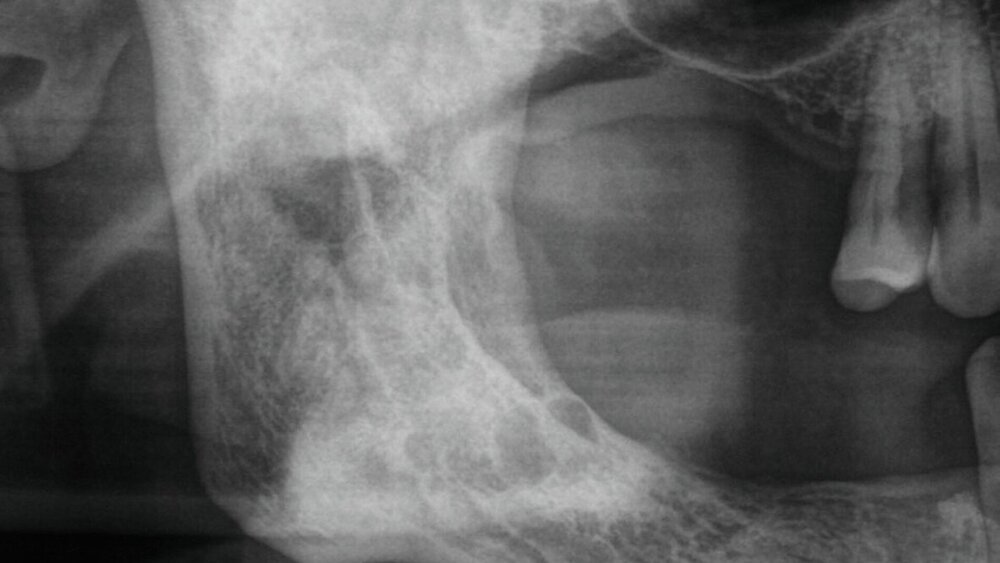

Während sich in den folgenden Jahren vor allem eine rückläufige Läsion mit Verknöcherung des ehemaligen Zystenlumens zeigte, stellte sich der Patient 2024 mit einer plötzlich progredienten Hypästhesie des rechten Nervus alveolaris inferior vor. Bei Verdacht auf Vorliegen eines Rezidivs des bekannten Ameloblastoms erfolgte eine Panoramaschichtaufnahme (Abbildung 1), die den Verdacht erhärtete. Im anschließend folgenden DVT zeigten sich multiple, kreisförmig-zystische Aufhellungen die sich vom Kieferwinkel bis regio 45 erstreckten (Abbildung 2).